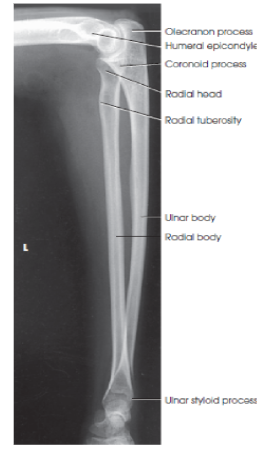

What structures are shown in a lateral forearm image?

entire forearm, including wrist and distal humerus in a true lateral position

eval - What structures should be superimposed in a lateral forearm image?

the radius and ulna at their distal end

the radial head over the coronoid process

humeral epicondyles

eval - what happens to the radial tuberosity in a lateral forearm position?

it faces anteriorly